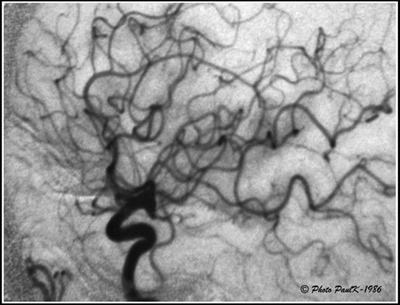

En radiographie, la technique du masque est surtout utilisée lors d’examens particuliers destinés à explorer le système artériel ou veineux.

Pour radiographier le système artériel ou veineux, il est nécessaire d’injecter un produit qui soit opaque aux rayons X.

C’est ce que l’on appelle communément, le produit de contraste.

Masque-ArterioAL’inconvénient de ce procédé est que les parties du corps les plus denses, les os en particulier, sont aussi opaques aux rayons X.

Cela rend donc la lecture et l’interprétation des radios plus délicates.

L’astuce photographique consiste dont à masquer sur le cliché, ces éléments indésirables.

Sur le cliché de droite, correspondant à une artériographie carotidienne, on ne voit pratiquement plus la structure de la boite crânienne ce qui permet d’obtenir une très bonne lisibilité du système artériel et veineux.

En prenant une radiographie de la zone à examiner avant toute injection, nous obtenons une image dont il est facile d’obtenir une image positive avec un film particulier (masque).   —> Ce qui est blanc devient noir et réciproquement.

Il sera alors facile de superposer ce masque au cliché obtenu, après injection du produit de contraste, pour obtenir une nouvelle image par soustraction, sur laquelle n’apparaîtront que les éléments attendus.